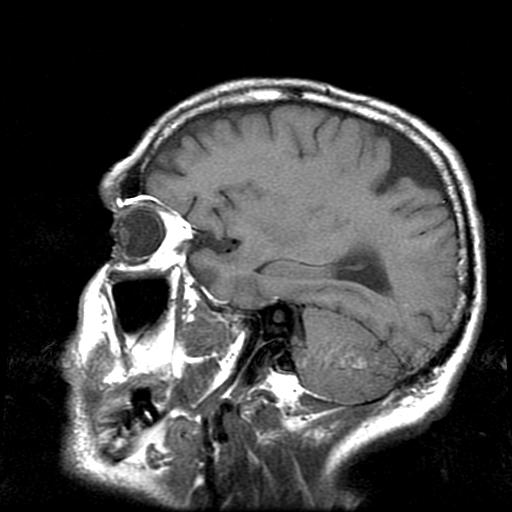

Funnel shaped dark feature near top- back of head appears to be low density  consistent with cerebral spinal fluid (pretty much salt water) that surrounds and cushions the brain matter.

This looks more serious than it apparently is. I did get the MRI scans (2/29/08) to diagnose brain related symptoms, and discovered this.

Based on the appearance and location this is probably residual from a basketball injury  approximately 3 years ago. Head struck the floor pretty hard and after the game I noticed mild concussion symptoms.

While the Dr. who read these images made three possible diagnosis. None seems a very good fit to me (infarct, cyst, or soft spot?). I don't even have a good name for it, "CSF pocket"? I call it Lake Stout.

They say to take an aspirin and call them in 6 months for more scans (if you're not dead).